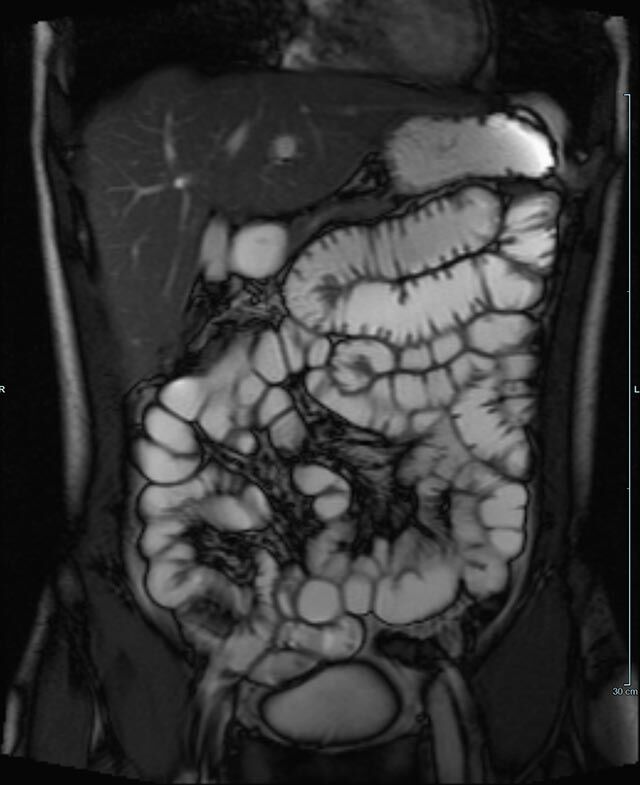

Abdomen/Becken

• Darm

• Darstellung bzw. Kontrolle im Verlauf bei perianalen Fisteln und Abszessen

• Verlaufskontrolle des Lokalbefundes nach Rektumentfernung bei Karzinom